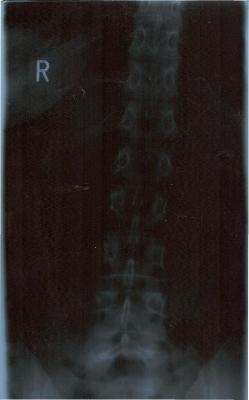

Ach so bevor ich vergesse: von meinem Rücken bestehen 4 Röbis, die den gesamten Rücken zeigen. Das Bild von der LWS ist eigenartig: erst unten gerade und dann geht sie schräg nach rechts hoch. Meine Orhopädin meint, die LWS sei kerzengerade, der FA aus Bochum meint, da hätte ich beim der Aufnahme einen Druck von links bekommen (ich stand aber allein und - für mich - gerade vor dem Gerät. Mich hat nichts und niemand gedrückt - interessiert die Ärzte aber nicht). Leider konnte ich dem Menschen in Bochum auch nur die zeigen, da die CD`s noch im Krankenhaus unterwegs sind.

Ich kann auch das Röntgenbild, wo die WS so schräg ist, einstellen. Du klingst nach viel Erfahrung und kannst sicherlich besser beurteilen als ich!

Hier ist das Röbi wo die Ärzte meinen, die LWS sei kerzengerade:

Zum zum Röbi an sich: Es ist wirklich komisch, wie schief das nach oben geht. Ich vermute daher, dass deine eigentliche Krümmung darüber, also in der BWS sitzt oder du eine langgezogene Krümmung hast, die in der BWS weitergeht und dann wieder zur Mitte geht. Aber genau deshalb braucht man eine Ganzwirbelsäulen-Aufnahme!!

ich wollte erst schauen, ob das mit den Bildern funktionert - daher Testforum. Der erste Versuch ist ja auch schief gegangen, doch im Testforum problemlos löschbar. Jetzt hat es geklappt, daher habe ich sie jetzt auch hier. So können sich auch andere dazu äußern (obwohl Deine Meinung schon sehr fachfraulich klingt und ich fast glaube, dass mein Schicksal besiegelt ist!!!). Jedenfalls tut es mir gut, dass jemand anderes auch meint, dass meine WS eben doch nicht kerzengerade aussieht - ich freue mich (dachte nämlich schon, ich wäre bekloppt).

es wäre wirklich interessant, wie deine Wirbelsäule im Ganzen aussieht. In der LWS hast du zumindest schonmal keine Rotation, was positiv ist. Evtl. ist es ja nur eine Fehlhaltung oder eben eine typische Begleit-Skoliose bei Rundrücken. Deshalb ist auch ein seitliches Röntgenbild zur Diagnostik notwendig.Jedenfalls tut es mir gut, dass jemand anderes auch meint, dass meine WS eben doch nicht kerzengerade aussieht - ich freue mich (dachte nämlich schon, ich wäre bekloppt).

Ansonsten sieht meine Mutter dem Termin sehr ruhig entgegen während ich schon jetzt eine leichte Nervosität fühle. Wir haben von uns beiden Röbis der LWS (auf CD, leider komme ich mit dem Runterladen nicht klar und kann sie nur einsehen aber nicht abspeichern). Meine Mutter hat den gleichen "Bogen" wie ich - nur dass bei ihr die Wirbel sich drehen. Außerdem sieht man bei meinr HWS einen deutlichen Bogen nach links (die LWS geht ja nach rechts bei uns beiden). Ich glaube, so langsam muss ich mich mit Tatsachen anfreunden